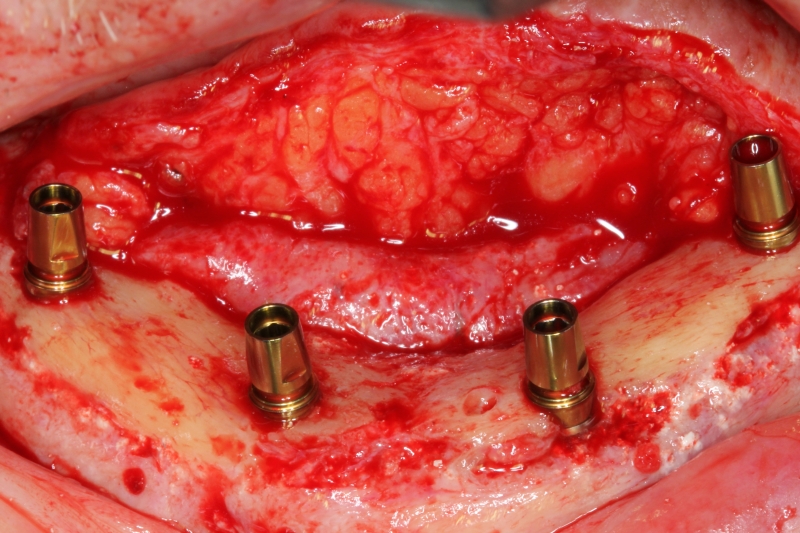

12/14 - Insertion of 4 implants

Block augmentation with maxresorb®, collprotect® membrane & autologous bone blocks - Prof. Dr. Dr. D. Rothamel